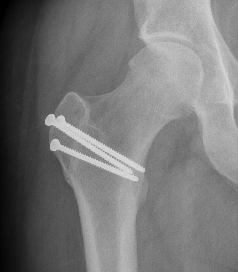

- ORIF displaced subcapital